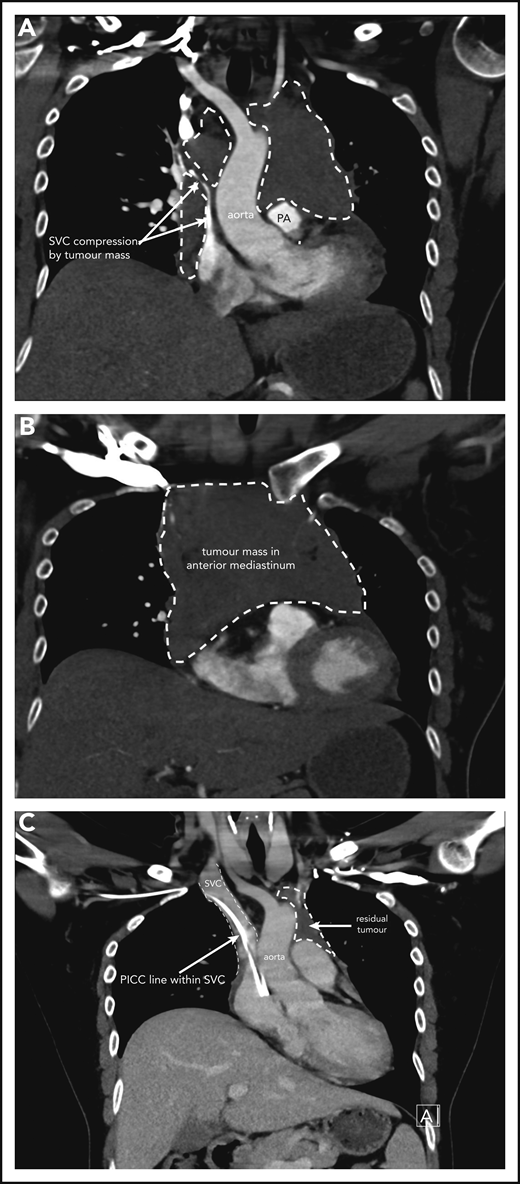

Case 1 of patient with primary mediastinal B-cell lymphoma presenting at 31weeks gestation. (A) Coronal section chest CT scan with contrast at diagnosis, pretreatment. Illustrates significant compression of SVC by tumor mass (within broken lines) on right and demonstrating extent of mass also on left superior to pulmonary artery (PA). (B) Transverse section chest CT scan with contrast at diagnosis, pretreatment. Illustrates extent of anterior mediastinal tumor mass. CT imaging suggested possible moderate-sized pericardial effusion found on echocardiography to be a small effusion. (C) Coronal section chest CT scan with contrast at completion of treatment. Normal caliber SVC with a peripherally inserted central catheter (PICC) line in situ. Small volume of residual tumor (within broken lines). Subsequent PET-CT scan demonstrated no activity confirming a complete metabolic response.